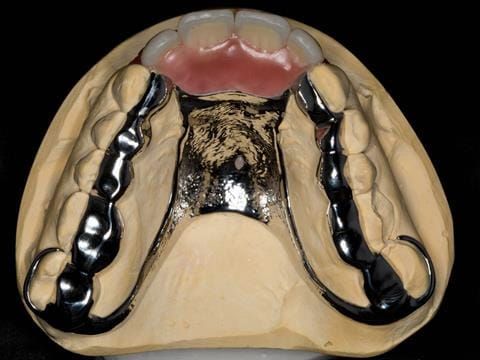

- Extract the upper 2-2 teeth and replace with an interim acrylic based partial denture. Reline the interim denture over 9 - 12 months, replacing with a definitive cobalt chromium based partial denture. The definitive denture would ideally be designed as an occlusal protective splint to reduce the the potential for mechanical wear and breakages of the moderately/heavily restored maxillary dentition. In addition, should further upper teeth require extraction they could be added on to the denture cobalt chromium framework - therefore a new prosthesis would not be required as future teeth are lost. This option would produce an excellent aesthetic outcome. This is the option the patient chose to have.

Following consultation and second discussion appointment the patient chose to have option 3 namely, a maxillary cobalt chromium based partial denture/protective occlusal splint. The clinical situation and treatment process is shown in detail below with photographs. The patient was successfully rehabilitated with this and her quality of life considerably improved. The clinical work was provided by Finlay and the technical work by Rowan.